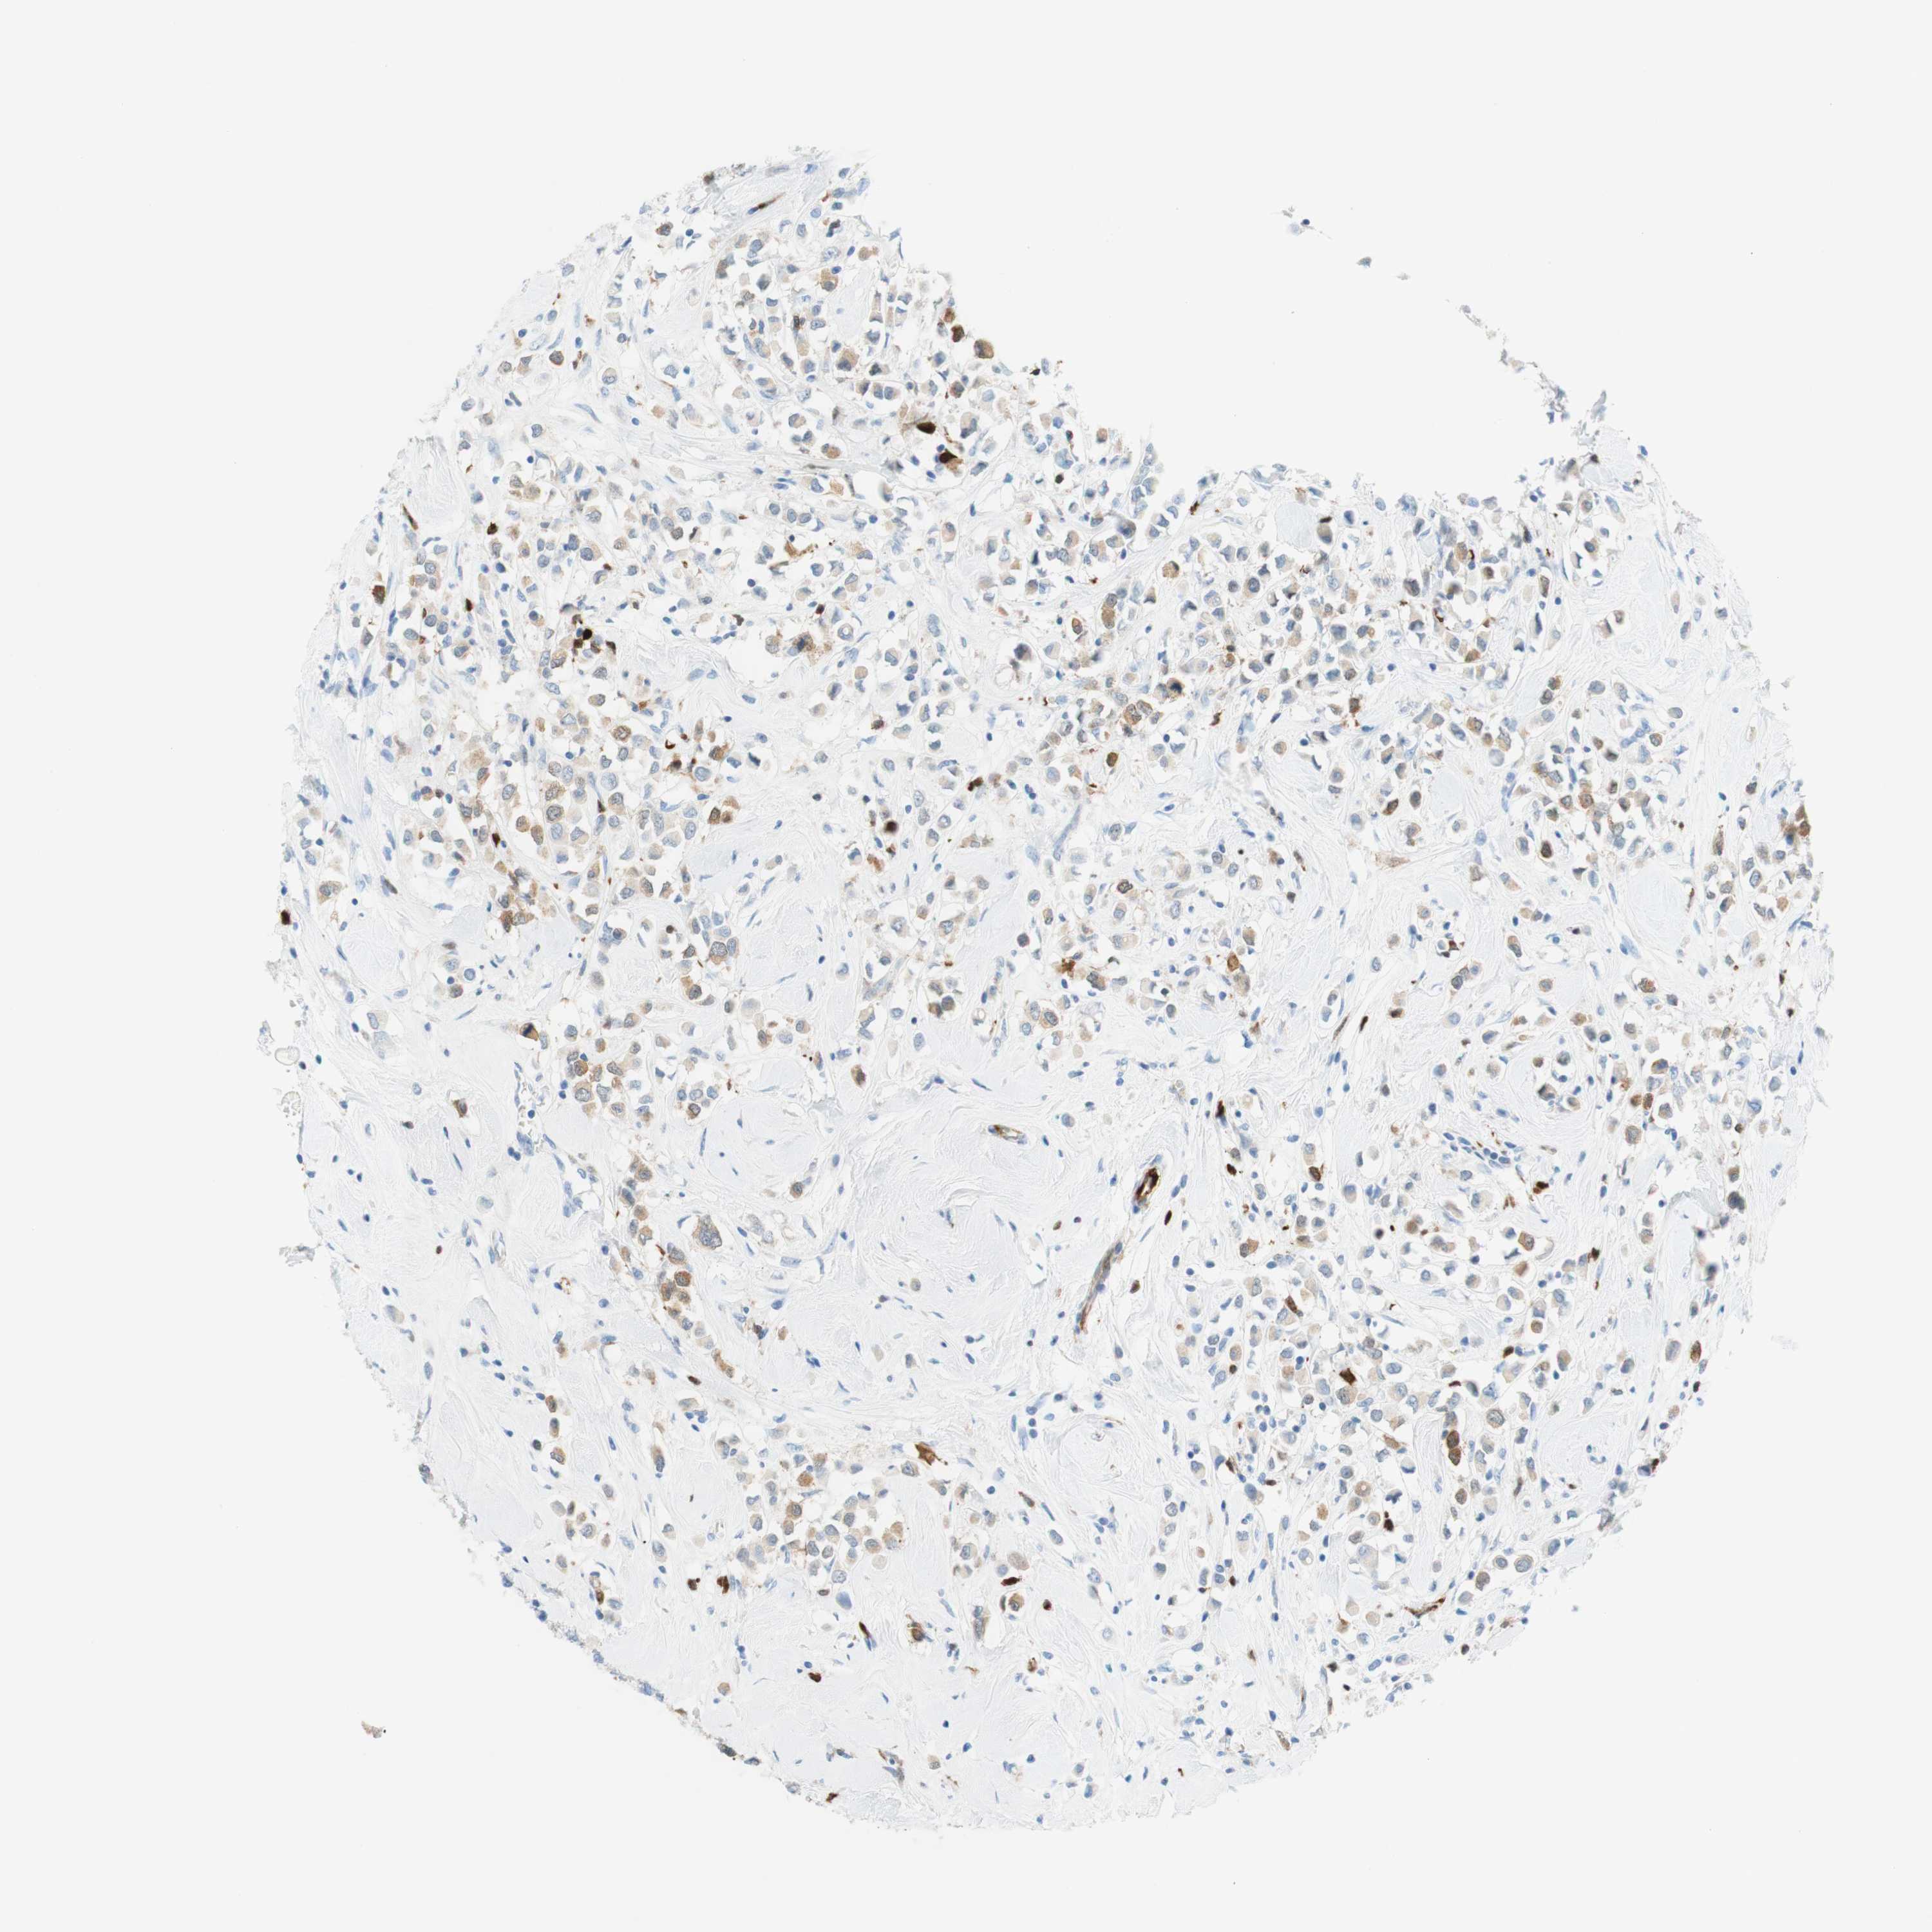

BRCA TCGA BRCA VALIDATION PROTEIN EXPRESSION

ANTIBODIES

AND

VALIDATION